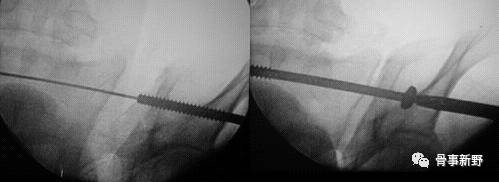

(4)骶髂螺钉的定位:导针进针点在髂后上、下嵴之间,髂后上嵴外约2横指、坐骨大切迹上方2横指。透视确认入针点,正位、入口位及出口位满意后(在正位图像中导针尖部位于在S1椎体阴影中,出口位导针指向S1椎体中间1/3份,导针位于S1椎体上终板附件的骨质最厚处)。打入导针到中线,一共穿过3层皮质骨,透视位置确认后进行钻孔。

(5)置入合适长度的 7.3mm空心拉力螺,再次多角度透视确认螺钉位置。

(6)第二枚导针:第二枚导针打入S1椎体的前1/3,位于椎体前半部的下方;进针方向为腹侧倾斜20°,头侧倾斜20°。技术要求较高。

(4)骶髂螺钉必须沿着S1椎弓根块进入椎体,保持全程在骨内。第一枚螺钉在上方,正位透视位于椎体中部靠近上终板,第二枚螺钉位于椎体前半部的下方。( 参考文献:Marvin Tile主编,邱贵兴主译,骨盆与髋臼骨折,2006)